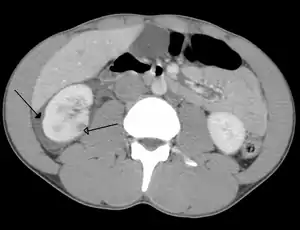

| ترومای شکم باعث کوفتگی در کلیه شده و خونریزی(نوک پیکان) در اطراف کلیه در سیتیاسکن دیده میشود. | |